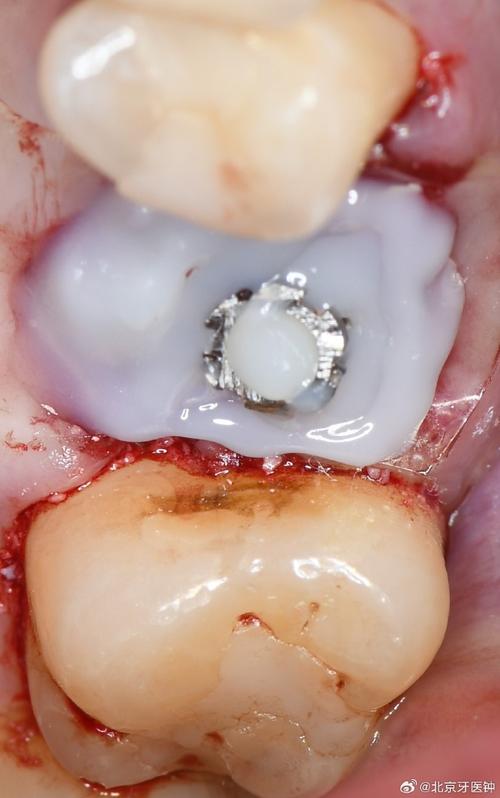

| 临时修复 | 对符合条件的患者,安装临时牙冠,调整咬合避免早接触;无法即刻负重者可缝合牙龈。 | 临时牙冠需降低咬合高度,防止种植体承受过大咬合力。 |